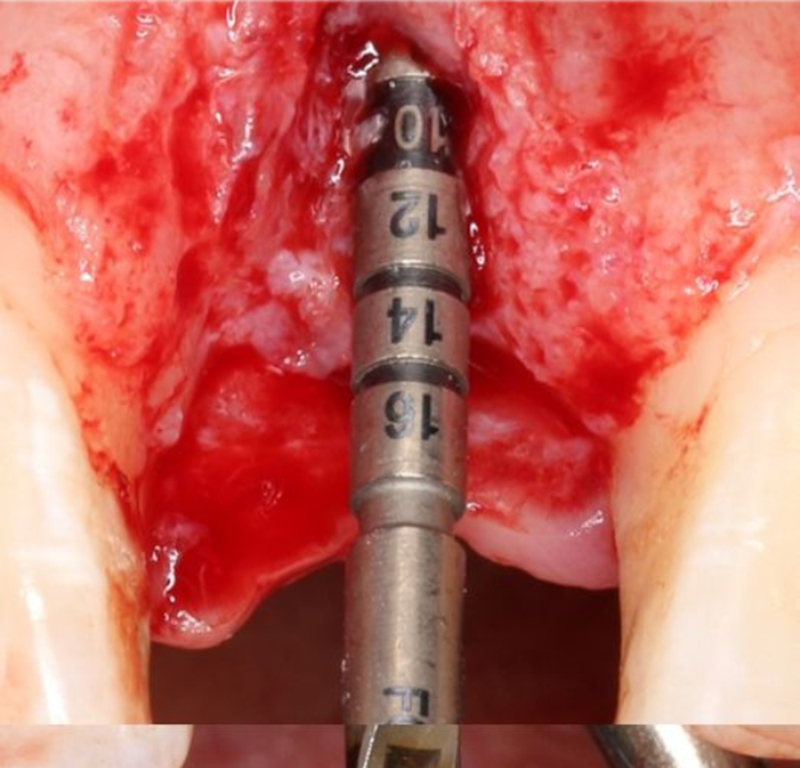

2.2mm 先鋒鉆確定植入深度及軸向△

在實時導(dǎo)航系統(tǒng)中,實時引導(dǎo)先鋒鉆按照術(shù)前設(shè)計種植體軸向及深度進行擴孔△